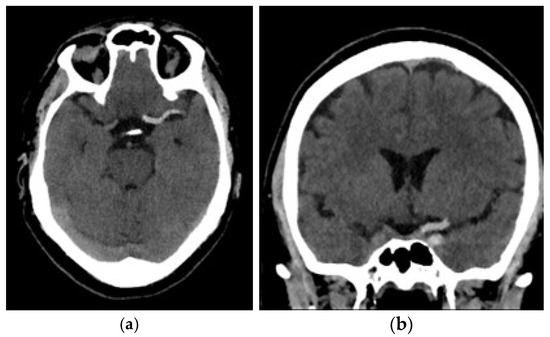

2.3. Image Acquisition

2.4. Segmentation and Feature Extraction